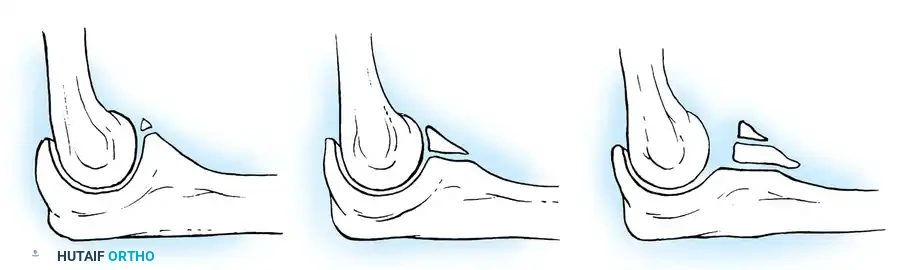

In cases of chronic radial head dislocation (often missed acutely or associated with plastic deformation of the ulna), simple open reduction is insufficient. The Hirayama Technique utilizes an ulnar osteotomy to overcorrect the angular deformity, thereby pulling the radial head back into the joint via the interosseous membrane.

TECHNIQUE 33-5: Osteotomy of the Ulna (Hirayama et al.)

- Preparation: Inflate a pneumatic tourniquet. Make a posterolateral skin incision exposing the radiohumeral joint and proximal third of the ulna. Excise intra-articular scar tissue.

- Osteotomy: Perform a subperiosteal osteotomy of the ulna 5 cm distal to the olecranon.

- Distraction and Angulation: Distract the osteotomy by 1 cm to lengthen the ulna.

- For Anterior Dislocation: Correct by posterior angulation of the ulna.

- For Lateral Dislocation: Correct by medial angulation of the ulna.

- Fixation: Secure the osteotomy with a metal plate bent to approximately 15 degrees. Ensure the radial head rests perfectly within the radial notch of the ulna without excessive radiocapitellar pressure.

- Closure: Approximate the anconeus. Do not repair the annular ligament, as this can restrict rotation.

- Postoperative Care: Apply a plaster splint in 90 degrees of flexion and full supination for 4 weeks, followed by aggressive active range of motion.

Fig. 33-36 Overcorrection with posterior convexity for anterior dislocation.

Fig. 33-37 Overcorrection with medial convexity for lateral dislocation.